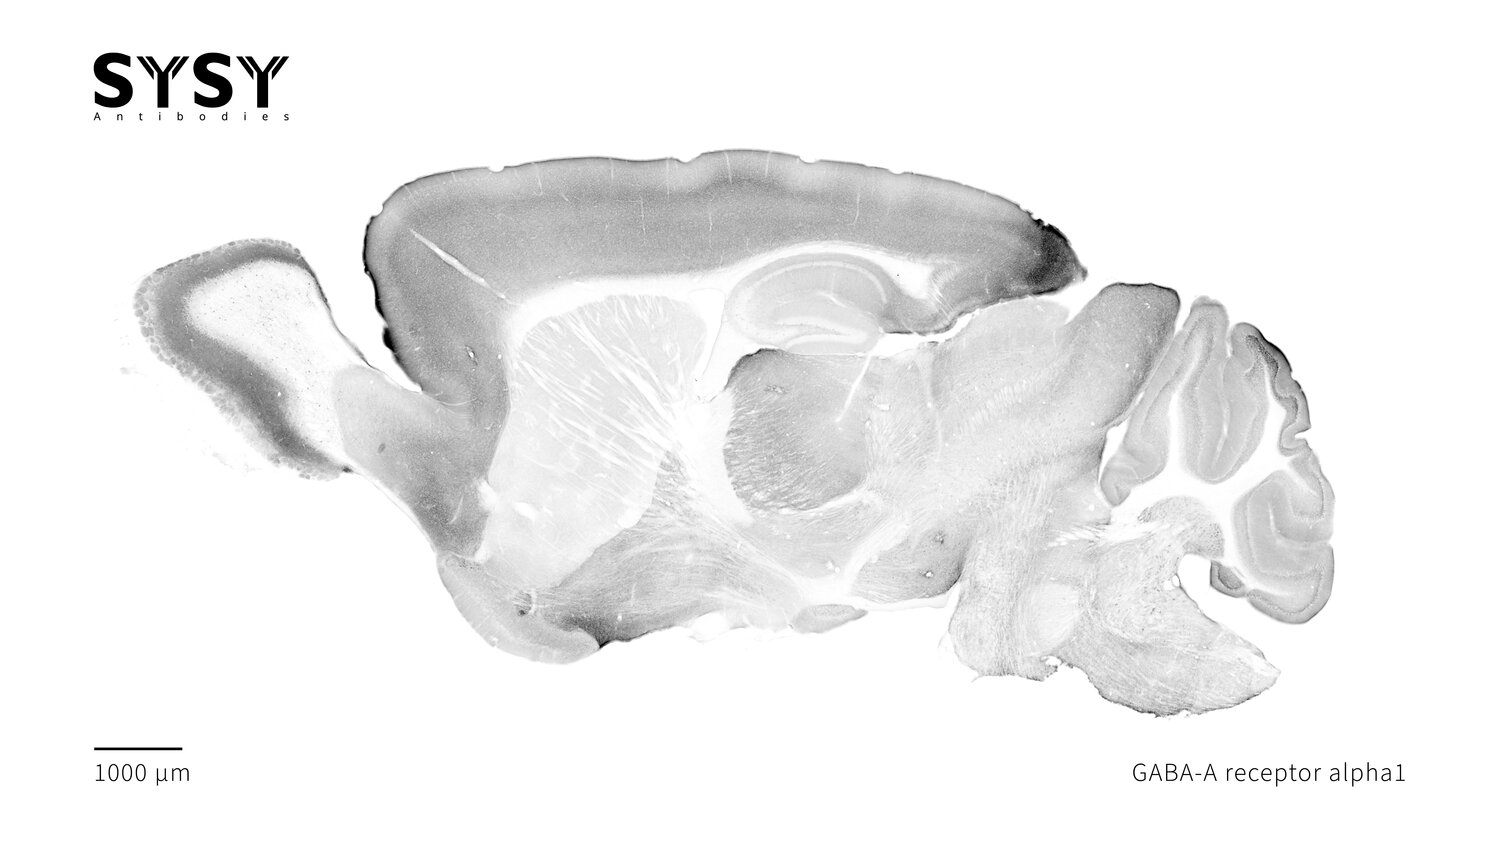

GABA-A receptor alpha1

Indirect immunostaining of a formaldehyde fixed sagittal mouse brain section with mouse anti-GABA-A receptor alpha1 antibody (cat. no. 224 211, dilution 1 : 500).